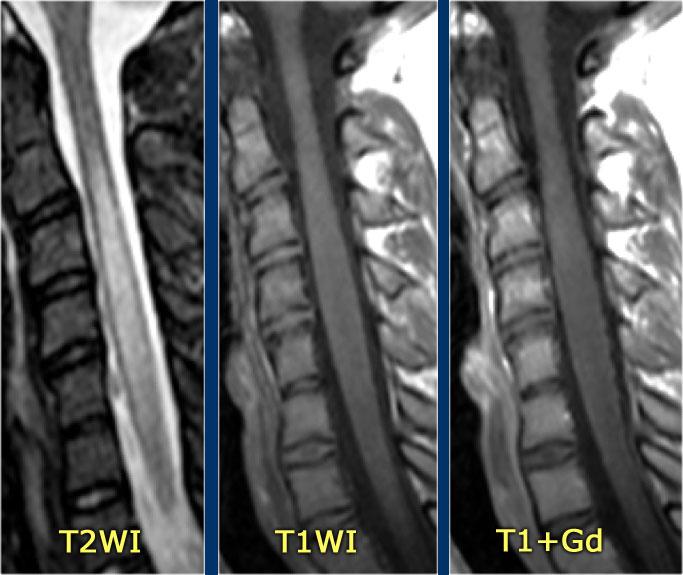

Hình ảnh mặt phẳng đứng dọc cho thấy một đoạn dài tăng tín hiệu trên chuỗi xung T2W.

Hình ảnh mặt phẳng ngang cho thấy phần lớn tủy sống bị tổn thương.

Đây là hình ảnh của bệnh nhân nam 31 tuổi với các triệu chứng đau đầu, rối loạn đi tiểu, bí tiểu, mức cảm giác tại C3.

Phân tích dịch não tủy (CSF) cho thấy 400/3 tế bào (không có dấu hiệu nhiễm trùng) và nồng độ protein tăng nhẹ.

Hình ảnh cho thấy bệnh lý tủy đoạn dài với tổn thương toàn bộ mặt cắt ngang.

Không có phù nề và không có ngấm thuốc tương phản từ.

Hình ảnh không điển hình cho xơ cứng rải rác (MS) hay u, do đó chúng tôi nghĩ đến ATM – viêm tủy cắt ngang cấp tính.

Đây là hình ảnh của một trường hợp TM điển hình.

Có tăng tín hiệu đa đoạn trên STIR và chuỗi xung T2W kèm theo phù nề nhẹ.

Phần lớn tủy sống trên đường kính ngang bị tổn thương.

Không có ngấm thuốc tương phản từ, đây thường là đặc điểm thường gặp trong TM.

Đôi khi có thể thấy ngấm thuốc dạng vá không đều.

Khi có ngấm thuốc tương phản từ, việc phân biệt TM với u tế bào hình sao (astrocytoma) có thể rất khó khăn.

Bên trái là hình ảnh của bệnh nhân nam 60 tuổi mắc u tế bào hình sao.

Bệnh nhân nhập viện với đau vùng ngực và rối loạn cảm giác chi dưới trái, tiếp theo là liệt nửa người trái.

Có tăng tín hiệu đa đoạn trên chuỗi xung T2W kèm phù nề nhẹ, tương tự như hình ảnh đã thấy trong các trường hợp TM.

Trên CE-T1W có vùng ngấm thuốc tương phản từ.

Vùng ngấm thuốc có hình thái nghiêng về u hơn, nhưng việc phân biệt vẫn còn khó khăn.

Lưu ý vùng tăng tín hiệu ở đoạn tủy ngực dưới và các mạch máu giãn xung quanh trên chuỗi xung T2W.

Trên chuỗi xung T1W có tiêm thuốc tương phản từ, có hiện tượng ngấm thuốc nhẹ.